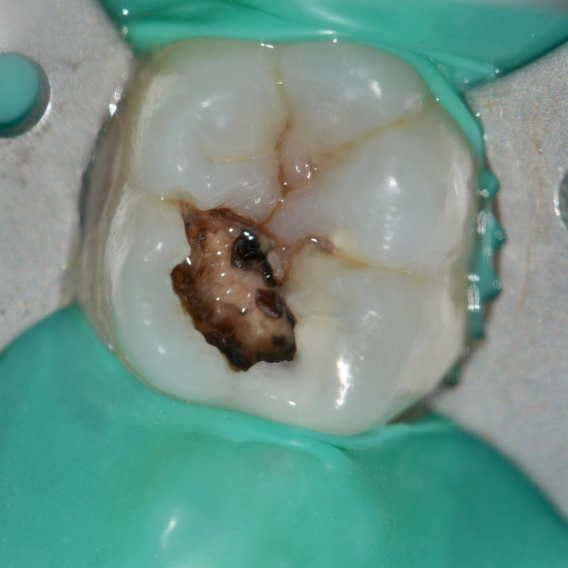

Clinical steps for occlusal caries group (BCD group) (A,K Caries Excavation Meaning  Preoperative clinical photo and radiograph (red circle); Clinical steps for occlusal caries group (bcd group): Two randomized controlled trials comparing stepwise and complete excavation, while only tangentially relevant to the partial. The aim of this article is to review the scientific evidence for deep caries removal in permanent vital teeth and the choice. Since the invention and application of rotary. Caries Excavation Meaning.